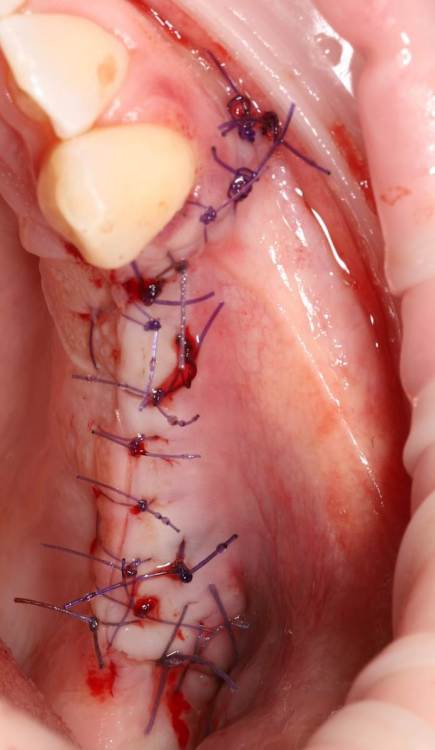

Ponchik Опубликовано 27 ноября, 2022 Поделиться Опубликовано 27 ноября, 2022 Неделю назад проведён синуслифтинг. Через 4-5 дней заболело горло. Вчера начался "НАСМОРК" Сегодня осмотр. Сделал КТ. Обработал местно антисептиками. Назначил Цефотаксим, Полидексу, Аквамарис (до этого был амоксиклав) отпустил до четверга. Вопрос: может зря я решил наблюдать? Надо было раскрыть и всё убрать? Просто растерялся. Первый раз за 6лет (как начал делать) синус проинфицировался. Ссылка на комментарий

Ponchik Опубликовано 27 ноября, 2022 Автор Поделиться Опубликовано 27 ноября, 2022 3 часа назад, TIGER сказал: @Ponchik дренаж работает?(соустье) Да. Работает. Отделяемое из носа есть и по кт видно как вся эта куча графта, с» и жидкости тянется к соустью. Срез просто выбран по середине графта в зоне операции. Вопрос второй назрел. Кто виноват? Всё закисло на первой неделе. Лоскут лежит вроде нормально. Можно считать инфицирование произошло во время операции? Грешить на обработку поля, рук и инструментов? Или? Пациент очень боялся именно такого исхода. Я выдал больничный и человек старался из дома нос не высовывать. Ссылка на комментарий